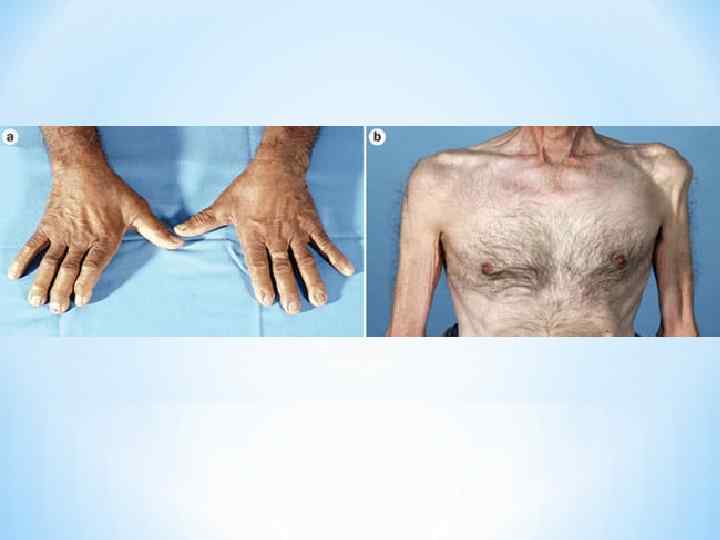

* Для БАС в большинстве случаев характерна асимметричность * симптоматики. * В атрофированных обнаруживаются фасцикуляции(локальные или распространенные) * В типичном случае начало заболевания с похудания мышц тенара одной из кистей с развитием слабости аддукции (приведения) и оппозиции большого пальца, (обычно асимметрично), что затрудняет схватывание большим и указательным пальцами и приводит к нарушениям тонкого моторного контроля в мышцах кисти. Больной ощущает затруднения при подбирании мелких предметов, при застегивании пуговиц, при письме. * Затем, в процесс вовлекаются мышцы предплечья, а кисть приобретает вид «когтистой лапы» . Через несколько месяцев развивается сходное поражение другой руки. Атрофия, постепенно распространяясь, захватывает мышцы плеча и плечевого пояса. * Одновременно с этим или позже часто развивается поражение бульбарных мышц: фасцикуляции и атрофия языка, парез мягкого неба, атрофия мышц гортани и глотки, что проявляется в виде дизартрии (нарушения речи), дисфагии (нарушения глотания), слюнотечения. Мимические и жевательные мышцы обычно поражаются позже других групп мышц. По мере развития заболевания становится невозможным высовывание языка, надувание щек, вытягивание губ в трубочку. Иногда развивается слабость разгибателей головы, из за чего больной не может держать голову прямо. При вовлечении в процесс диафрагмы наблюдается парадоксальное дыхание (на вдохе живот западает, на выдохе выпячивается).

* Для БАС в большинстве случаев характерна асимметричность * симптоматики. * В атрофированных обнаруживаются фасцикуляции(локальные или распространенные) * В типичном случае начало заболевания с похудания мышц тенара одной из кистей с развитием слабости аддукции (приведения) и оппозиции большого пальца, (обычно асимметрично), что затрудняет схватывание большим и указательным пальцами и приводит к нарушениям тонкого моторного контроля в мышцах кисти. Больной ощущает затруднения при подбирании мелких предметов, при застегивании пуговиц, при письме. * Затем, в процесс вовлекаются мышцы предплечья, а кисть приобретает вид «когтистой лапы» . Через несколько месяцев развивается сходное поражение другой руки. Атрофия, постепенно распространяясь, захватывает мышцы плеча и плечевого пояса. * Одновременно с этим или позже часто развивается поражение бульбарных мышц: фасцикуляции и атрофия языка, парез мягкого неба, атрофия мышц гортани и глотки, что проявляется в виде дизартрии (нарушения речи), дисфагии (нарушения глотания), слюнотечения. Мимические и жевательные мышцы обычно поражаются позже других групп мышц. По мере развития заболевания становится невозможным высовывание языка, надувание щек, вытягивание губ в трубочку. Иногда развивается слабость разгибателей головы, из за чего больной не может держать голову прямо. При вовлечении в процесс диафрагмы наблюдается парадоксальное дыхание (на вдохе живот западает, на выдохе выпячивается).

* На ногах обычно первыми атрофируются передняя и боковая группы мышц, что проявляется «свисающей стопой» и походкой типа степпаж (больной высоко поднимает ногу и выбрасывает ее вперед, резко опуская). * Характерно, что мышечные атрофии имеют избирательный характер. На руках наблюдаются атрофии тенара, гипотенара, межкостных и дельтовидных мышц. На ногах вовлекаются мышцы. осуществляющие тыльное сгибание стопы. В бульбарной мускулатуре поражаются мышцы языка и мягкого неба. * Пирамидный синдром развивается, как правило, на ранней стадии БАС и проявляется оживлением сухожильных рефлексов. Вслед за этим нередко развивается нижний спастический парапарез. В руках повышение рефлексов сочетается с мышечными атрофиями. Поверхностные брюшные рефлексы исчезают по мере прогрессирования процесса. Симптом Бабинского наблюдается в половине случаев заболевания. * Могут быть нарушения чувствительности. У 10% больных наблюдаются парестезии в дистальных отделах рук и ног. Боли, порою выраженные, обычно ночные, могут быть связаны с тугоподвижностью суставов, длительной неподвижностью, спазмами вследствие высокой спастичности, с крампи (болезненными мышечными спазмами), депрессией. Выпадения чувствительности не характерны. * Глазодвигательные нарушения не характерны и встречаются на терминальной стадиях заболевания. * Нарушения функций тазовых органов не характерны, но в далеко зашедшей стадии может наблюдаться задержка или недержание мочи. * Умеренно выраженные когнитивные расстройства проявляются у 50% больных. У 5% больных развивается деменция лобного типа, которая может сочетаться с паркинсоническим синдромом. * Особенностью БАС является отсутствие пролежней даже у парализованных лежачих больных.

* На ногах обычно первыми атрофируются передняя и боковая группы мышц, что проявляется «свисающей стопой» и походкой типа степпаж (больной высоко поднимает ногу и выбрасывает ее вперед, резко опуская). * Характерно, что мышечные атрофии имеют избирательный характер. На руках наблюдаются атрофии тенара, гипотенара, межкостных и дельтовидных мышц. На ногах вовлекаются мышцы. осуществляющие тыльное сгибание стопы. В бульбарной мускулатуре поражаются мышцы языка и мягкого неба. * Пирамидный синдром развивается, как правило, на ранней стадии БАС и проявляется оживлением сухожильных рефлексов. Вслед за этим нередко развивается нижний спастический парапарез. В руках повышение рефлексов сочетается с мышечными атрофиями. Поверхностные брюшные рефлексы исчезают по мере прогрессирования процесса. Симптом Бабинского наблюдается в половине случаев заболевания. * Могут быть нарушения чувствительности. У 10% больных наблюдаются парестезии в дистальных отделах рук и ног. Боли, порою выраженные, обычно ночные, могут быть связаны с тугоподвижностью суставов, длительной неподвижностью, спазмами вследствие высокой спастичности, с крампи (болезненными мышечными спазмами), депрессией. Выпадения чувствительности не характерны. * Глазодвигательные нарушения не характерны и встречаются на терминальной стадиях заболевания. * Нарушения функций тазовых органов не характерны, но в далеко зашедшей стадии может наблюдаться задержка или недержание мочи. * Умеренно выраженные когнитивные расстройства проявляются у 50% больных. У 5% больных развивается деменция лобного типа, которая может сочетаться с паркинсоническим синдромом. * Особенностью БАС является отсутствие пролежней даже у парализованных лежачих больных.